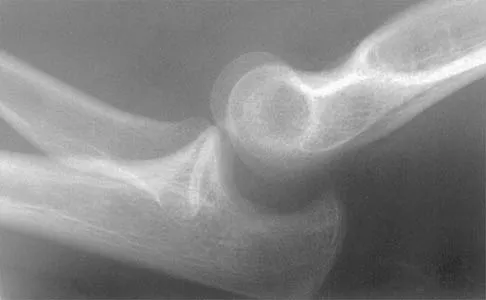

Question 37

Management of a grade IV osteochondritis dissecans lesion of the capitellum should consist of

Explanation